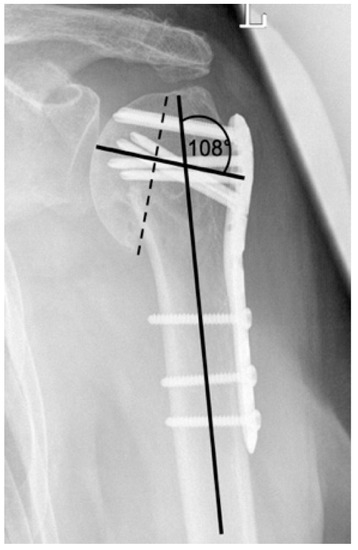

| Complication Type | Exemplary Images by X-rays or Pattern Images | Definition |

|---|---|---|

| 1 | ![]() | Complication Type 1 is defined by a mild, stable varus or valgus displacement (<20°) of the humeral head without resulting in a screw cutout through the humeral head cortex. |